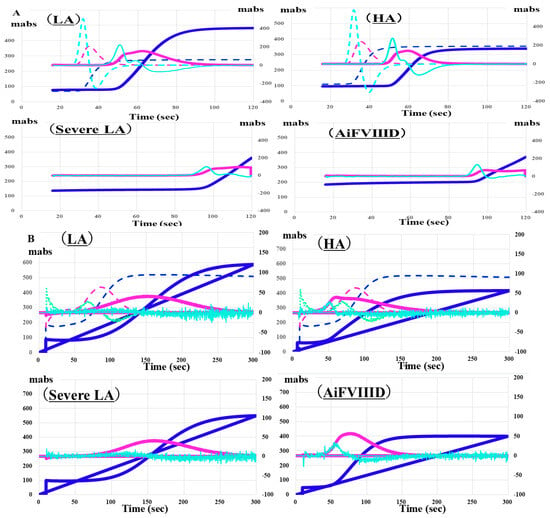

Regarding the CWA, no significant differences were observed in CWA-APTT between patients with hemophilia A and those with moderate LA or between AiFVIIID and those with severe LA [27]. PT was prolonged in patients with LA or severe LA, but not in patients with AiFVIIID or hemophilia A, suggesting that PT or sTF/FIX might be useful for distinguishing between LA and AiFVIIID [37] (Figure 7). A markedly low peak height of CWA-APTT was also effective in differentiating AiFVIIID from hemophilia A and LA [38]. It has been reported that a decrease in the peak height of CWA-APTT is more effective than an extension of the peak time in CWA-APTT for diagnosing hemophilia A or LA and predicting bleeding risk [39,40].

Figure 7.

Clot waveform analysis of APTT (A) and sTF/FIXa (B) in patients with LA, severe LA, HA and AiFVIIID. Although the peak times of CWA-APTT are prolonged in patients with LA, severe LA, HA, and AiFVIIID, they are not significantly prolonged in patients with HA and AiFVIIID. APTT, activated partial thromboplastin time; sTF/FIXa, small amount of tissue factor-induced coagulation factor IX activation assay; LA, lupus anticoagulant; HA, hemophilia A; AiFVIIID, acquired autoimmune FVIII deficiency; navy line, fibrin formation curve; pink line, first derivative curve (velocity); light blue, second derivative curve (acceleration); solid line, patient; dotted line, control. CWA-APPT showed a similar pattern between LA and HA and between severe LA and AiFVIIID, and CWA-sTF/FIXa showed a similar pattern between LA and severe LA and between HA and AiFVIIID.